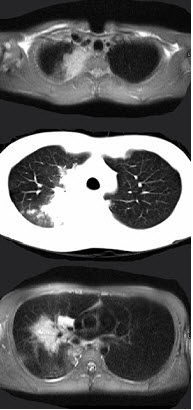

女,34岁,咳嗽,咯血半月余,请结合影像学检查,选出最可能的诊断( )

A:纵隔畸胎瘤

B:淋巴瘤

C:胸腺瘤

D:神经源性肿瘤

E:肺癌